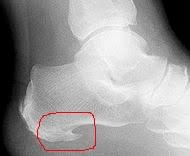

A sarokcsont csontkinövése, fájdalma (calcaneodynia)

A saroktáji fájdalom viszonylag gyakori panasz. A sarok területe a járás során igen nagy terhelésnek van kitéve, így bármilyen károsodás, gyulladás, túlterhelés hamar saroktáji fájdalomhoz vezet. A leggyakoribb okok, melyek a láb hátulsó részén fájdalmat okozhatnak:

- talpi sarkantyú

- hátsó sarkantyú

- az Achilles ín gyulladása, sérülése

- a sarokcsont cisztája

- a sarokcsont törése

A leggyakoribb, legtöbb panaszt okozó elváltozás a saroktájékon a sarkantyú. A fájdalmat tulajdonképpen nem a talpi csontkinövés – sarkantyú – okozza, hanem a láb túlterhelése miatti csonthártya gyulladás. A csontkinövés csak elhúzódó esetekben alakul ki a csonthártya gyulladás következtében, és csak igen ritkán nő akkorára, hogy műtéti eltávolítást igényeljen. Mivel a fájdalom oka a gyulladás, így a kezelés is elsősorban a gyulladás csökkentésére irányul, nem a csontkinövés eltávolítására.

A fentiekhez hasonló okokból alakulhat ki a sarokcsont hátsó felszínén az Achilles ín tapadásánál is sarkantyú, melynek oka az Achilles ín túlterhelése, gyulladása, az ezen a területen zajló csonthártya gyulladás, elhúzódó esetekben mészfelrakódás. Ez ritkább kórkép, de itt a csontkinövés általában zavaróbb a cipő nyomása miatt, így gyakrabban kényszerülünk műtéti eltávolításra. Röntgen felvételen mind a talpi, mind a hátulsó sarkantyú jól látható.

Mindkét elváltozásre jellemző a reggeli, elindulás előtti un. ibdítási fájdalom, később a nap folyamán a panszok enyhülnek, de gosszabb pihenés után újra jelentkeznek.

Bizonyos esetekben röntgen felvételre, igen ritkán tomográfiás (CT) vagy mágneses rezonanciás (MR) vizsgálatra is szükség lehet a panaszok okának tisztázására.

A saroktáji fájdalmak kezelésében nagy szerepe van a megfelelő, kényelmes cipőnek a megfelelő talpbetét használatának. Ezek lehetnek lyukasztott sarokpárnák, vagy szilikonos, zselés sarok-ékek..

Fizioterápia (lézer, terápiás röntgen, esetleg vízalatti ultrahang) a gyulladást jól csillapítja. Amennyiben a fentiek nem hoznak érdemi javulást, az érzékeny, gyulladt csonthártya fájdalma gyulladáscsökkentő injekciók adásával jól kezelhető.

Nagyon jó kezelési lehetőség a talpi szalag területére és a lábszár hajlító izomcsoportjára adott lökéshullám kezelés, mellyel az említett képletek lazítása és a panaszokat okozó csonthártya izgalom megszűnése érhető el. Szintén az utóbbi időben nyert teret a kezelésben az orvosi kollagén injekciók helyi beadása.

Legvégső esetben (igen ritkán) a csontkinövés műtéti eltávolítása hozhat megoldást az elhúzódó fájdalmakra.

A sarokcsonton belüli szerkezeti eltérések (ciszta, törés, daganat) szinte minden esetben műtéti megoldást igényelnek.